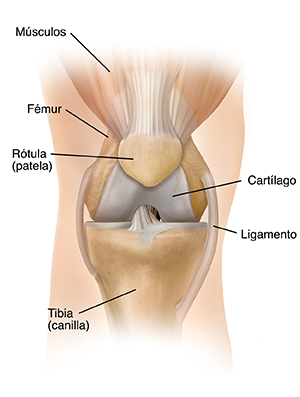

| Articulación de la rodilla normal. |